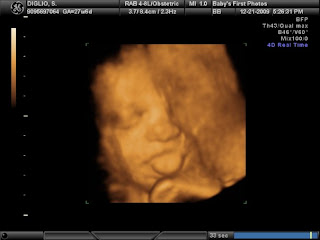

The moment that I saw her, I felt such joy, and a little confusion. She didn't look like I thought she would. I can't exactly pinpoint what was different but I thought she looked like she had Down Syndrome. But that couldn't be right. She never showed any of the markers in my sonograms. I mean she had a tongue protrusion in her 4d sonogram but all the technicians thought it was cute and nothing to worry about.